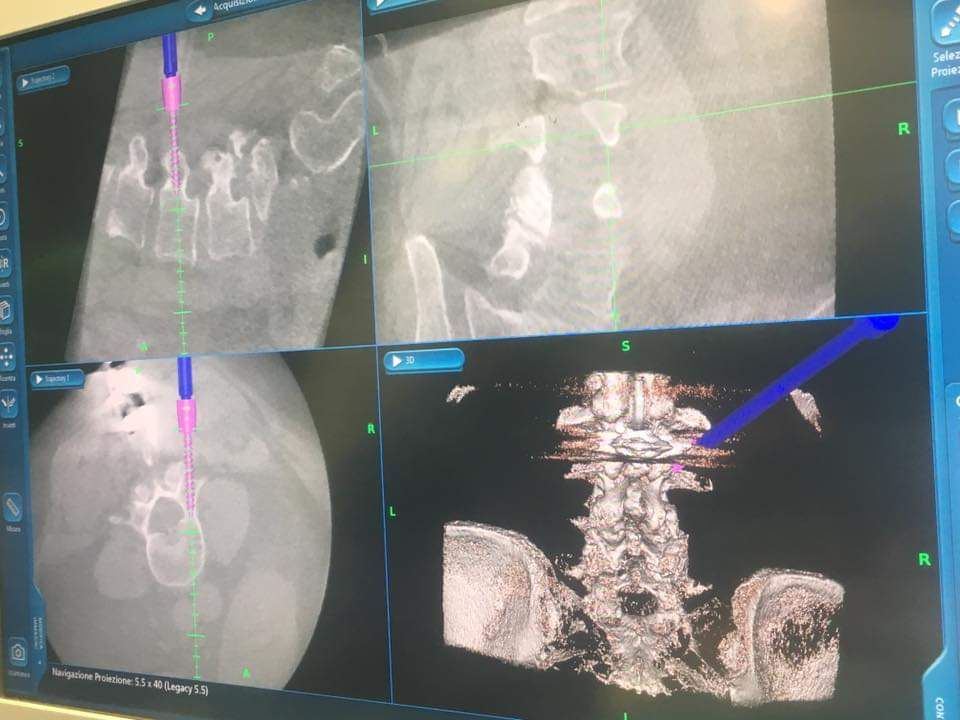

Mi occupo da più di 20 anni di neurochirurgia con tecnica mini-invsasiva, di patologie encefaliche e delle rachide vertebrale. Opero presso il Presidio Ospedaliero Garibaldi Nesima di Catania presso il quale sono dirigente medico di primo livello. Presso la stessa struttura ho l'incarico di eseguire e sviluppare tecniche mini-invasive neurochirurgiche.

• Chirurgia mini invasiva della colonna vertebrale

• Chirurgia mini-invasiva del rachide